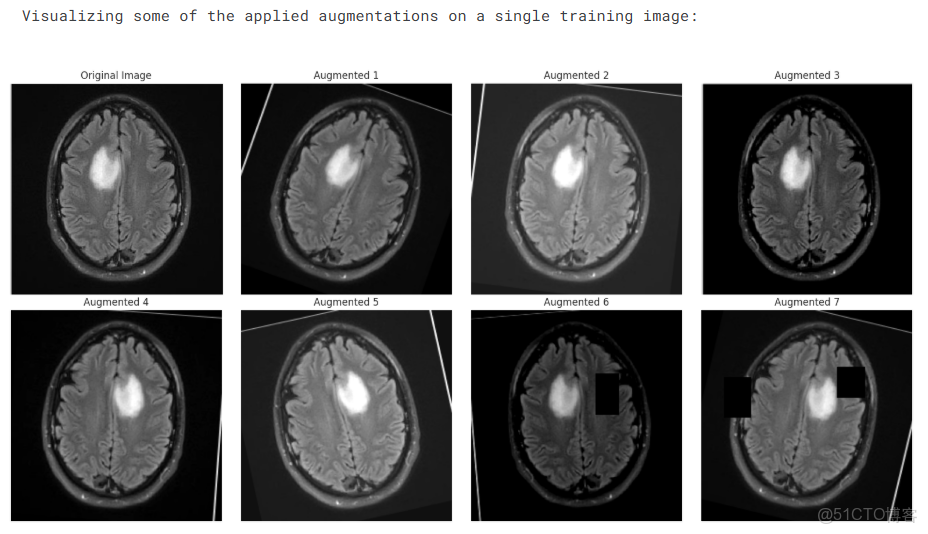

print("Visualizing some of the applied augmentations on a single training image:")

n_images = 8

original_image, _ = temp_train_dataset[0]

viz_transforms = A.Compose([t for t in temp_train_dataset.transforms if not isinstance(t, (A.Normalize, ToTensorV2))])

raw_img = cv2.imread(temp_train_dataset.df.loc[0, 'filepath'])

raw_img = cv2.cvtColor(raw_img, cv2.COLOR_BGR2RGB)

plt.figure(figsize=(16, 8))

plt.subplot(2, (n_images + 1) // 2, 1)

plt.imshow(raw_img)

plt.title("Original Image")

plt.axis('off')

for i in range(1, n_images):

augmented = viz_transforms(image=raw_img)['image']

plt.subplot(2, (n_images + 1) // 2, i + 1)

plt.imshow(augmented)

plt.title(f"Augmented {i}")

plt.tight_layout()

plt.show()

深度學習實戰-基於Vision Transformer的腦腫瘤MRI圖像識別_#深度學習_09